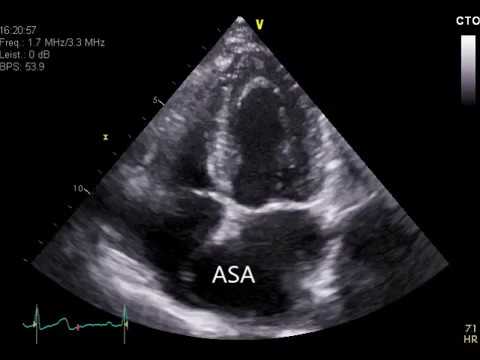

Atrial septal aneurysm symptoms. By definition when the atrial septum travels abnormally into either or both of the atria with each heartbeat it is considered to have an aneurysm. Bulges or balloons out of an atrial. Atrial septal aneurysm is a localized saccular deformity generally at the level of the fossa ovalis which protrudes to the right or the left atrium or both.

The atrial septal aneurysm ASA is a morphologic abnormality known to cause peripheral and pulmonary embolism. 3 atrial septal aneurysm patients report severe fatigue 60 1 a atrial septal aneurysm patient reports moderate fatigue 20 1 a atrial septal aneurysm patient reports mild fatigue 20 0 atrial septal aneurysm patients report no fatigue 0 What people are taking for it. Atrial septal aneurysms are simply an.

Atrial septal aneurysms produce abnormal heart sounds that can be detected even though a person is asymptomatic informs Clinical Cardiology. The atrial septum is similar to a wall separating t2 of the 4 chambers of the heart. An atrial septal aneurysm is an abnormally enlarged bulging and mobile atrial septum.

Atrial septal aneurysm is a congenital cardiac abnormality characterized by oscillation and aneurysmal bulging of atrial septal tissue into either or both atria during the cardiac cycle. Cerebrovasc Dis 2010. From birth to three years old a child has a lag in psychophysical development.